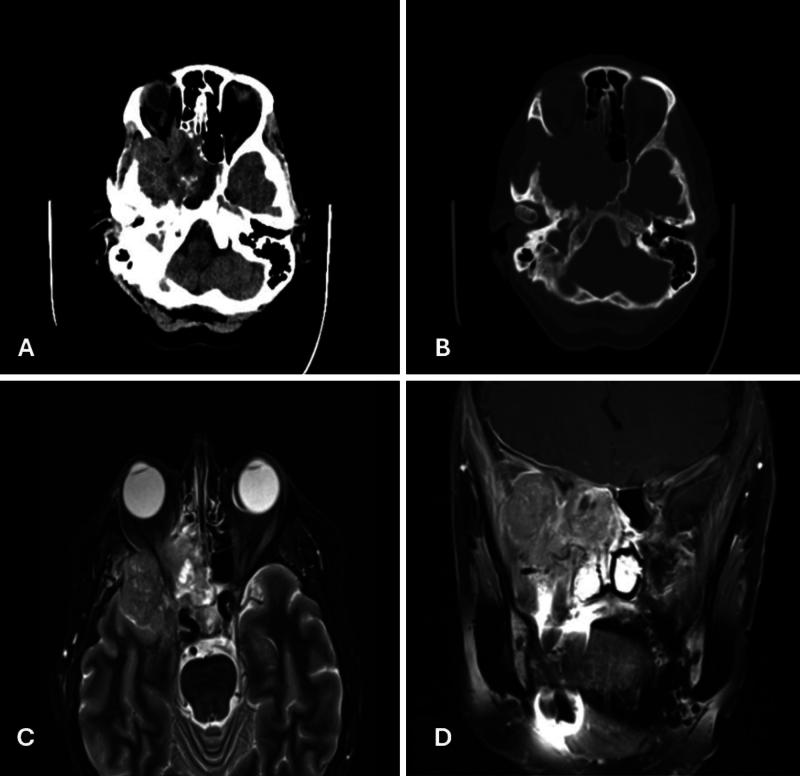

Decades after exposure each patient developed distinct brain tumors, a WHO grade I meningioma and a SMARCB1-deficient sinonasal carcinoma. Following craniotomies for resection and adjuvant therapy, only 1 patient's tumor progressed. Literature revealed radiation exposure analogous for these tumor's etiologies and identified various Chernobyl exposure groups parallel to these patients like cleanup workers, evacuees, and residents of highly contaminated areas and their descendants.

暴露数十年后,每位患者都患上了不同的脑肿瘤,一例是世界卫生组织一级脑膜瘤,另一例是SMARCB1缺陷型鼻窦癌。在进行开颅手术切除和辅助治疗后,只有1例患者的肿瘤进展。文献显示这些肿瘤病因的辐射暴露情况类似,并确定了与这些患者类似的切尔诺贝利暴露群体,如清理工人、撤离人员、高污染地区居民及其后代。